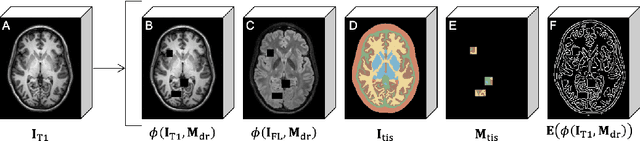

Accuracy validation of cortical thickness measurement is a difficult problem due to the lack of ground truth data. To address this need, many methods have been developed to synthetically induce gray matter (GM) atrophy in an MRI via deformable registration, creating a set of images with known changes in cortical thickness. However, these methods often cause blurring in atrophied regions, and cannot simulate realistic atrophy within deep sulci where cerebrospinal fluid (CSF) is obscured or absent. In this paper, we present a solution using a self-supervised inpainting model to generate CSF in these regions and create images with more plausible GM/CSF boundaries. Specifically, we introduce a novel, 3D GAN model that incorporates patch-based dropout training, edge map priors, and sinusoidal positional encoding, all of which are established methods previously limited to 2D domains. We show that our framework significantly improves the quality of the resulting synthetic images and is adaptable to unseen data with fine-tuning. We also demonstrate that our resulting dataset can be employed for accuracy validation of cortical segmentation and thickness measurement.